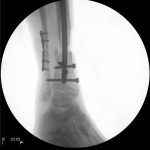

Chapman’s accident resulted in two open fractures in her legs that needed to be stabilized, and she lost a lot of skin that would need coverage, according to her orthopedic surgeon, Dr. Michael Rusnak. He used cement rods as a temporary stabilization that would later be replaced with metal.

“There was tissue damage around the bone, so there was an issue with blood flow,” he said. “I brought in (Dr.) James (McCarthy) to help. This was really a team approach.”

McCarthy covered the exposed rod and bone in Chapman’s right leg with muscle in the area, as he would in most cases. But her body rejected this technique with an infection. McCarthy went back in, transplanting a muscle from Chapman’s back, including its associated vein and artery, and meticulously attached the 2-millimeter blood vessels together — called microsurgery — to return the blood flow to Chapman’s damaged leg. The medical team had to do all of this while also ensuring her legs would have no deformities that could affect her mobility.